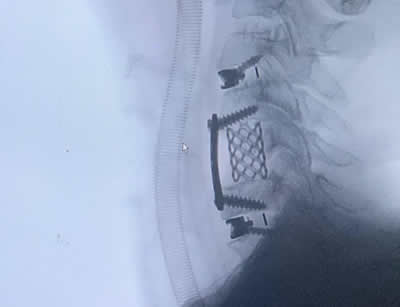

IMÁGENES

Galería de imágenes